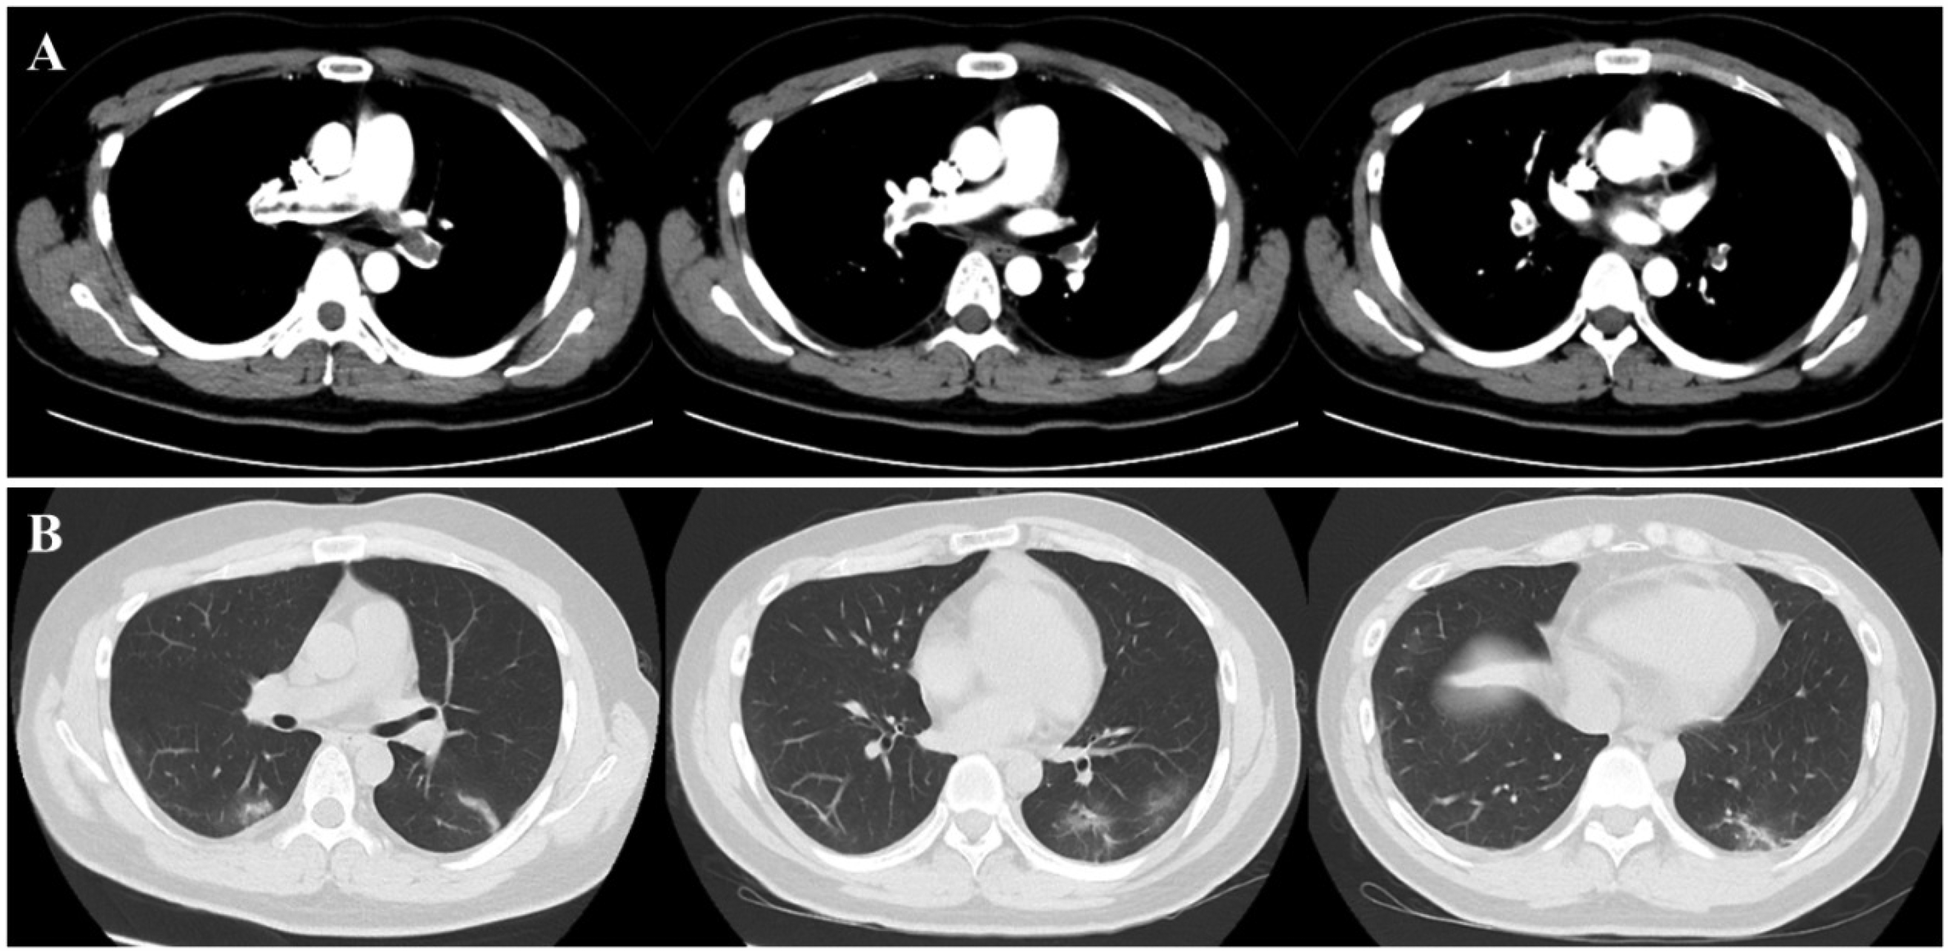

Figure 6

Present of thrombus in pulmonary veins and inflammatory changes in lung. The chest CT scan revealed the presence of multiple emboli in the pulmonary artery (A), as well as inflammation (B) in the lower lobes of both lungs.

After the third session of DFPP, the patient's coagulation report indicated a lack of clotting, leading to the discontinuation of his apheresis treatment. An intraluminal thrombus was found on the wall of the right femoral vein, and the patient was subsequently treated with low molecular weight heparin (LMWH). However, one week later, the patient developed a high fever (38.8°C) and his platelet count dropped dramatically from 202 × 109/L to 27 × 109/L (Figure 5). D-dimer levels also increased during the same period Figure 5. Ultrasound examination revealed the formation of a blood clot in the right common femoral vein, and a computed tomography (CT) scan detected multiple emboli in the pulmonary artery, as well as inflammation in the lower lobes of both lungs (Figure 6). The patient's 4 T score indicated a high probability of heparin-induced thrombocytopenia (HIT), and he tested positive for heparin-PF4 antibodies by ELISA.